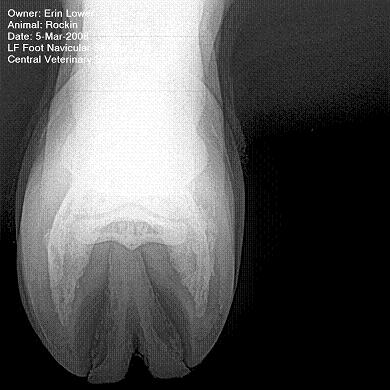

So, Rockin's x-rays were sent to a radiologist and he confirmed "normal" changes in the navicular bones for a horse her age, but slightly more significant ones in the right (sore) foot.

She also has sidebone in both fronts, but apparently that isn't causing any discomfort.

Finally, she has a "small chronic exostosis on the lateral aspect of the proximal phalanx" which, according to the radiologist, shouldn't be causing discomfort but I have read that these can be mild-to-moderately painful... I wouldn't mind another opinion on that.

I will attach as many images as possible from her x-rays (there are many different views). I don't have any pics of the feet as someone deleted them from my camera before I could download them. I'll try to take pics next time she is trimmed. Please, anyone with knowledge of hooves, give any opinions that you might have (especially Dr. O!)

Hello Erin and welcome back,

I cannot rule out lesions based on these images but I will take your radiologist's word that he does not see significant lesions. The exostosis on the RF would be above the level of a well conducted PDN which I believed blocked the lameness before?